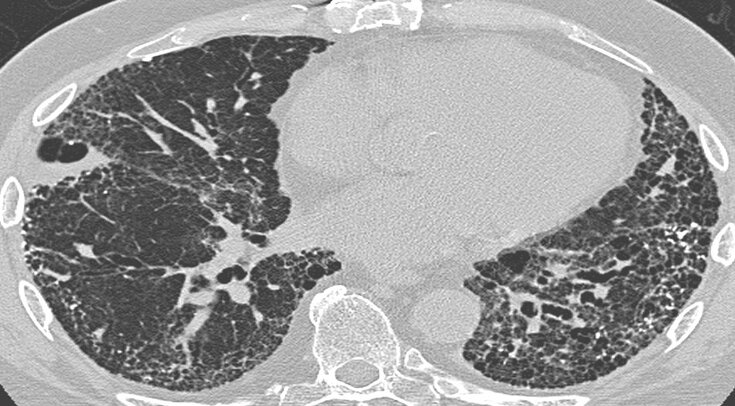

Наблюдение за почти двумя тысячами пациентов с пневмонией разной этиологии показало, что смертность от пневмонии при ковиде среди людей, находившихся на искусственной вентиляции легких (ИВЛ), не выше, чем при пневмонии, вызванной другими патогенами. Как сообщается в JAMA Network Open, ковид лишь увеличивал срок нахождения пациента на ИВЛ в отделении реанимации. По словам врачей ИВЛ пациентов с ковидной пневмонией необходимо проводить по тем же рекомендациям, что и при любой пневмонии.

В начале пандемии врачи считали, что дыхательная недостаточность при ковидной пневмонии имеет другие патофизиологические механизмы и ведет к большей летальности по сравнению с пневмониями, вызванными другими возбудителями. Из-за этого врачи пытались придумать новые, нестандартные схемы ИВЛ, однако они все были менее эффективными, чем уже известные алгоритмы ИВЛ.

Уильям Чекли (William Checkley) из Университета Джона Хопкинса с коллегами решили изучить различия в течение ковидной и не ковидной пневмоний у пациентов на ИВЛ. В ретроспективную выборку пациентов с ковидной пневмонией попали люди, госпитализированные в отделение реанимации и интенсивной терапии с дыхательной недостаточностью в период с марта 2020 по июль 2021 года. Ученые брали данные о пациентах с не ковидной пневмонией за период с июля 2016 по декабрь 2019 года. В исследование не включали данные пациентов, которым установлен диагноз вентилятор-ассоциированной пневмонии, и пациентов с трахеостомой.

В группе ковидной пневмонии оказалось 719 взрослых со средним возрастом 61,8 лет, 442 из которых мужчины, а 460 пациентов принадлежат к расовым меньшинствам. Не ковидными пневмониями болело 1127 пациентов, средний возраст которых 60,9 лет. 586 из них мужчины, а 655 — белые. При первичном сравнении групп выяснилось, что больные ковидом с большей вероятностью были не белыми мужчинами с диабетом и высоким индексом массы тела.

При ковиде ИВЛ начинали в среднем через 4,1 дня, а при не ковидной пневмонии — через 3,4 дня (р < 0,001). Ученые не обнаружили значимых изменений в параметрах при назначениях схем ИВЛ у пациентов с 2016 по 2019 год.

При первичном анализе ученые обнаружили, что пациенты с ковидной пневмонией находились в больнице дольше и имели больше шансов умереть в больнице, чем пациенты с не ковидной пневмонией. Выздоровевшие после ковидной пневмонии пациенты в среднем находились на ИВЛ 10 дней, тогда как пациентам с нековидной пневмонией требовалось всего 5 дней ИВЛ (р < 0,001).

Подробный статистический анализ показал, что пациенты с ковидом чаще страдали диабетом, хронической болезнью почек и иммуносупрессией. При этом у них реже встречалась хроническая обструктивная болезнь легких, хотя курили они больше, чем пациенты с не ковидной пневмонией. Ковидная пневмония повышала вероятность летального исхода на 21 процент, однако включение поправок в анализ показало, что вероятность летального исхода не отличалась у пациентов с пневмонией разной этиологии. Однако ковидная пневмония увеличивала срок нахождения пациента на ИВЛ примерно на 19 процентов.

Что касается показателей ИВЛ, то у пациентов с ковидной пневмонией требовался меньший дыхательный объем (VT) и большее давление в конце выдоха (PEEP) в течение первых семи дней ИВЛ. Однако подробный анализ показывает, что податливость (комплаенс) легких пациентов с ковидной пневмонией не отличалась от таковой у пациентов с не ковидной пневмонией на первой неделе ИВЛ, то есть нарушения функции дыхания были соразмерными.

Пока что врачи не могут точно объяснить, почему пациентам с ковидной пневмонией требуется больше времени на ИВЛ, чем пациентам с «обычной» пневмонией. Есть данные о том, что SARS-CoV-2 вызывает стойкое и медленно разрешающееся воспаление альвеол. Однако необходимы новые клинические и морфологические исследования, чтобы разобраться в природе этого явления. На данный момент, исследователи рекомендуют придерживаться стандартных протоколов проведения ИВЛ при ковиде, которые применяются при любых пневмониях.